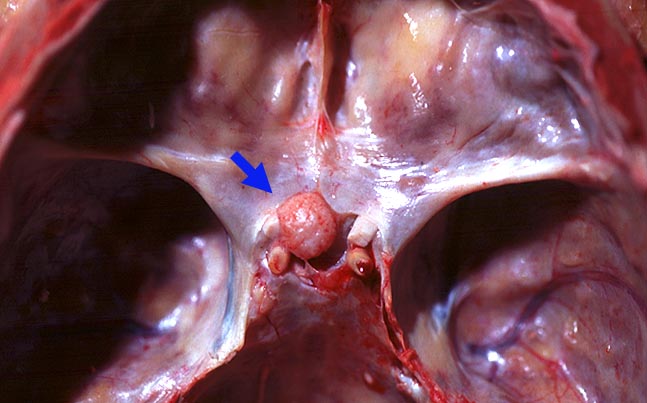

PathoPic – image database / PathoPic ID 2057 - Meningeom des Tuberculum sellae

Meningeom des Tuberculum sellae

Meningeom des Tuberculum sellae auf der Mittellinie, leicht nach links verschoben liegend. Feinhöckrige Oberfläche. Leichte Verformung des Nervus Opticus sinister kurz vor Eintritt in den Canalis opticus.

Berührung der Arteria cerebri media ohne Verformung und dorsale Verlagerung des Hypophysenstiels durch das Meningeom. Histologisch Meningeom vom transitionalen Typ.